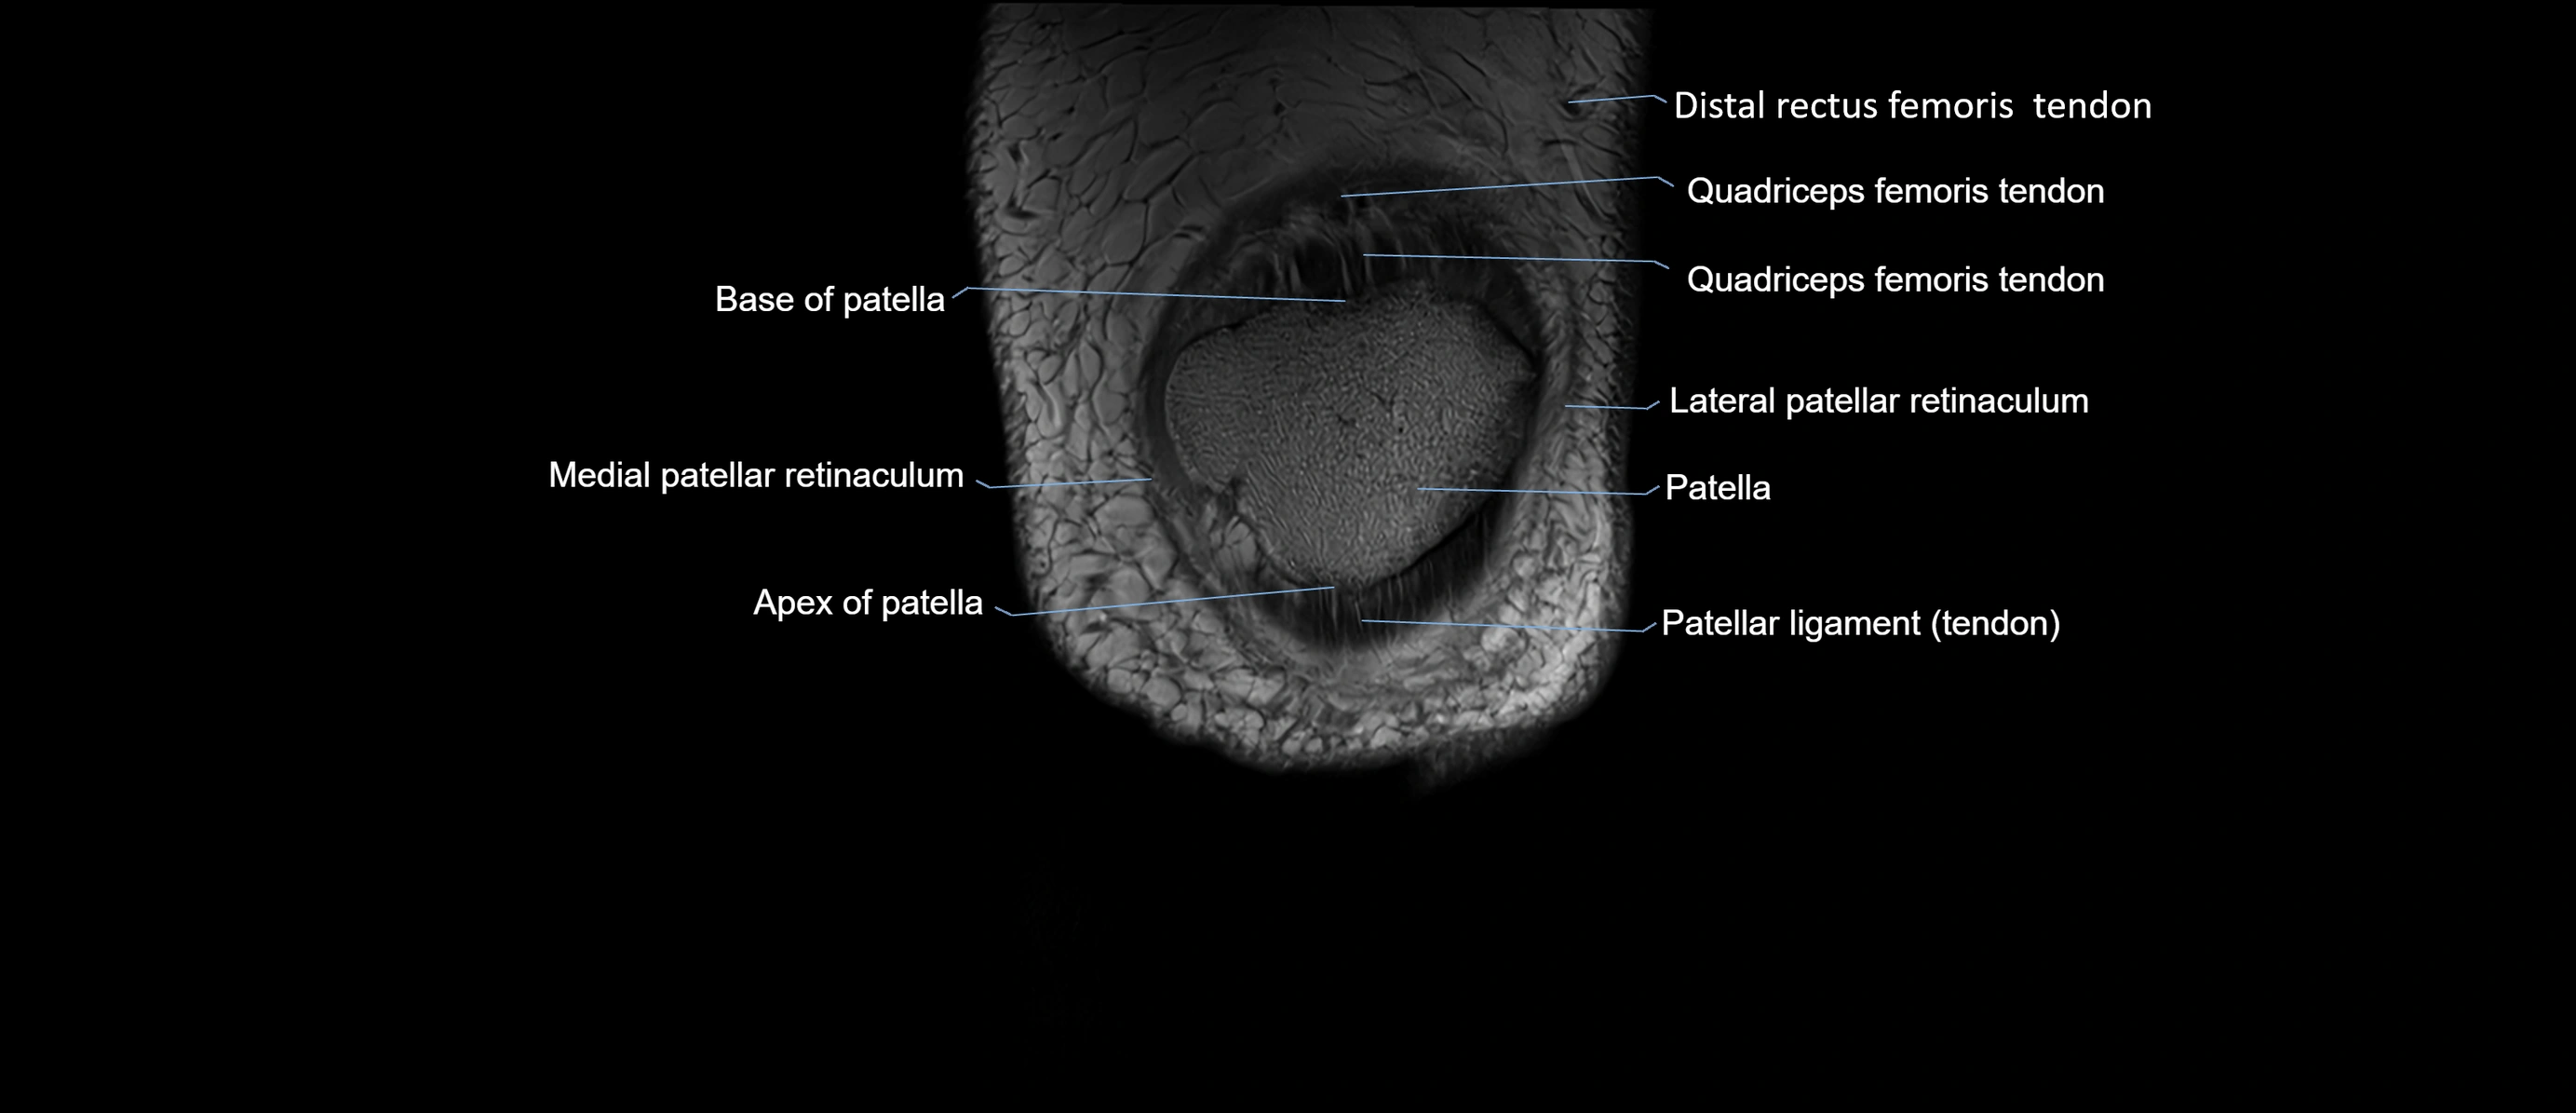

- Apex of patella

- Base of patella

- Lateral patellar retinaculum

- Medial patellar retinaculum

- Patella

- Patellar articular cartilage

- Patellar tendon (patellar ligament)